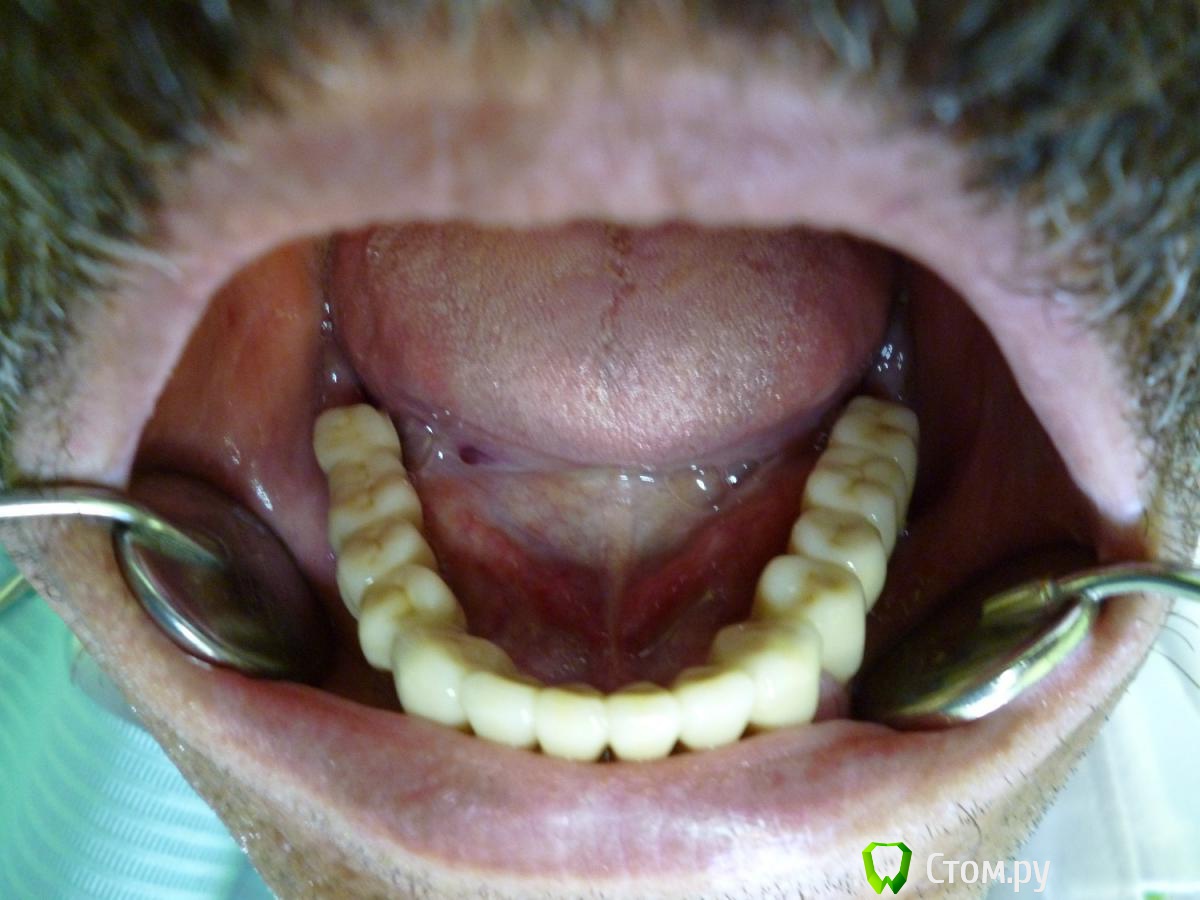

Troy Опубликовано 28 апреля, 2014 Поделиться Опубликовано 28 апреля, 2014 Вот такой рекольчик субпериостальников 5 лет прошло. Только камнями за НЧ кидать не надо . Это все таки моя глубокая молодость и за 5 лет мои взгляды сильно поменялись :). На синус пациент был категорически не согласен (интернет виноват),а хотел несъем2009 год2014 год. Жалоб нет. Так это выглядит сейчас. Ленты необнажены. Пардон за плохие фотки - фоткал на колегину мыльницуХотелось бы услышать Ваши комменты. 1 5 Ссылка на комментарий

Troy Опубликовано 28 апреля, 2014 Автор Поделиться Опубликовано 28 апреля, 2014 В третьем сегменте кость у имплантов ушла почти на 1/2, 2.7 удалять. Фото плохие, в Области 2.5 похоже свищ, резьба винтов тридцатой стороны выступает в полость рта и все в камнях. Мало?27 - его любимый зуб, он отказался его удалять еще 5 лет назад, пошли на поводу, пролечили покрыли, пока небеспокоит. В обл 25 свища нет, красное пятно артефакт на снимке фото плохие. Камней у него нет. Проблеммы в 3 сегменте действительно присутствуют. Но цель была показать СПИ.Извините что разачаровал .... :( А не новокузнецкие ли это "шедевры" ?Нет 1 1 Ссылка на комментарий

Troy Опубликовано 30 апреля, 2014 Автор Поделиться Опубликовано 30 апреля, 2014 уже одним синуслифтингом не обойтисьНе могли бы вы поподробнеее изложить свои мысли по этому поводу. А то как то уж совсем коротко получается... значит показалось Так точно! Вы действительно считаете что это хорошо?Я разве где-то сказал что это хорошо ??? Я попытался показать исход и что бывает с СПИ в средних сроках функционирования. Тем более что они пока еще в функции. Форум это же не только выставка всего самого лучшего. Или у вас боков не бывает? Не всегда получается быть умным и красивым... Извините что не поняли мои намерения. Я этим не похвастаться хотел. Да и на форуме не одного СПИ нет. Или поиск не работает... в третьем секторе еще до установки формирователя кость уже убежала от импланта?через 5 лет кость убежала вездеВсе правильно, как в воду смотрели. Как Вы думаете без реимплантации получиться в этом секторе. Хотя бы чисто теоретически...Очень интересно было бы Ваше мнение по поводу дальнейшей реабилитации ВЧ Заранее спасибо 1 Ссылка на комментарий